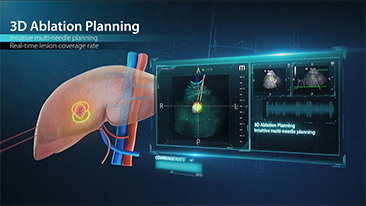

Le soluzioni Mindray Resona per la diagnostica per immagini generale consentono ai medici di ottenere diagnosi e trattamenti con risultati pi├╣ precisi ed efficaci grazie a sonde specifiche complete e a efficienti strumenti clinici applicativi.